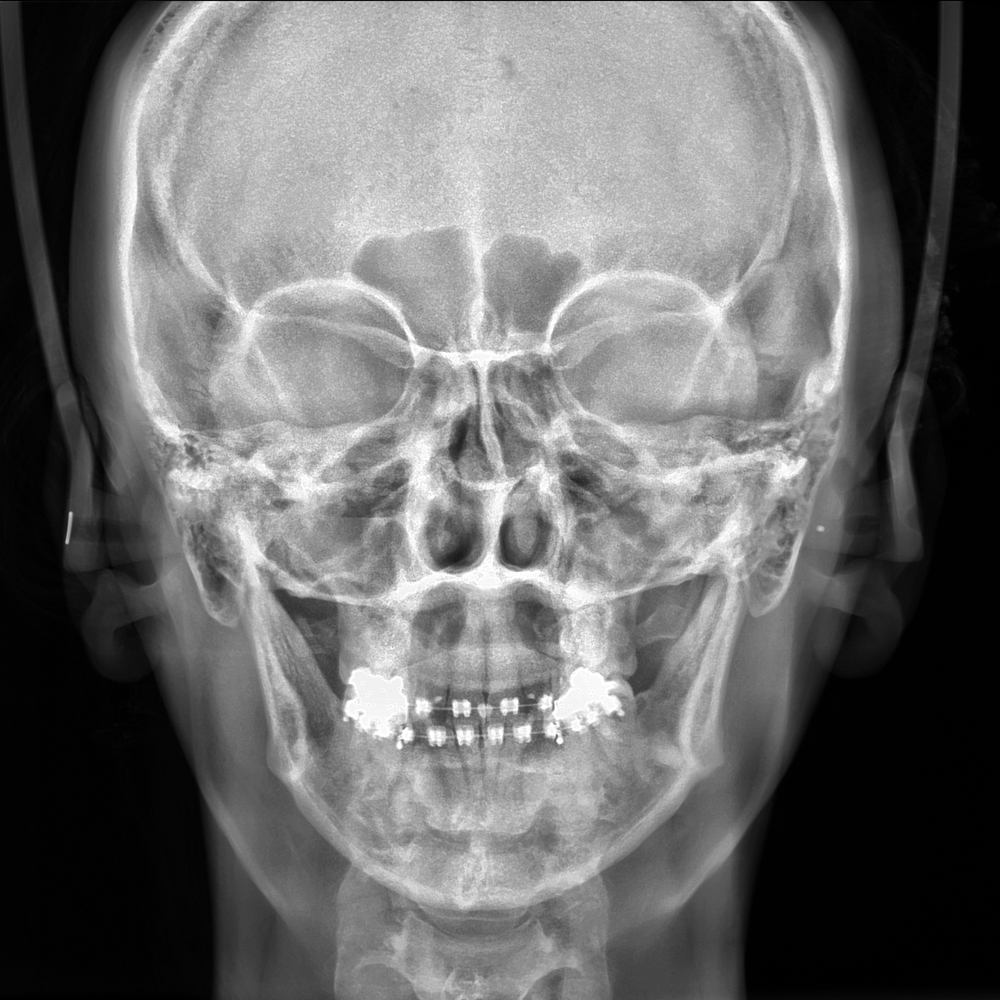

El Eagle 2D Pan/Ceph ofrece todos los exámenes en el perfil panorámico

(panorámica estándar, senos maxilares, baja dosis, bitewing, ATM, ortogonalidad perfeccionada, panorámica infantil y bitewing ortogonalidad perfeccionada)

y todos los exámenes en el perfil cefalométrico (Posteroanterior, Antero-posterior, 45 Grados, Lateral, Carpal, PA de Walters, Axial Bazal, Hirtz).